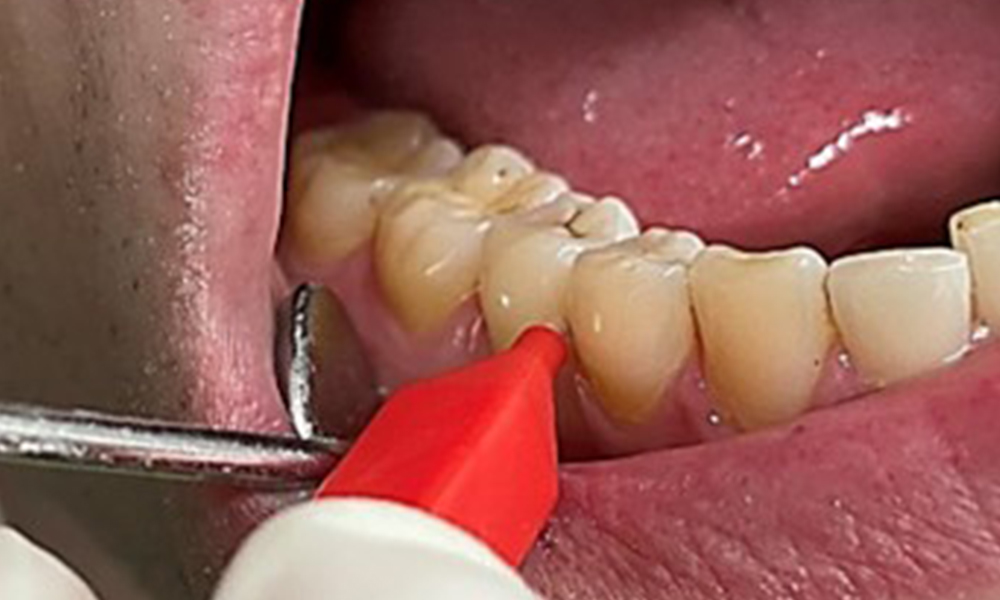

Discolouration caused by nicotine and tea consumption can be removed easily using an air polisher (Fig. 11).

Air polishing system use in the mandibular frontal lingual area (here, Proxeo Aura, W&H)

Fig. 11 Air polishing system use in the mandibular frontal lingual area (here, Proxeo Aura, W&H), © Dr R. Krapf